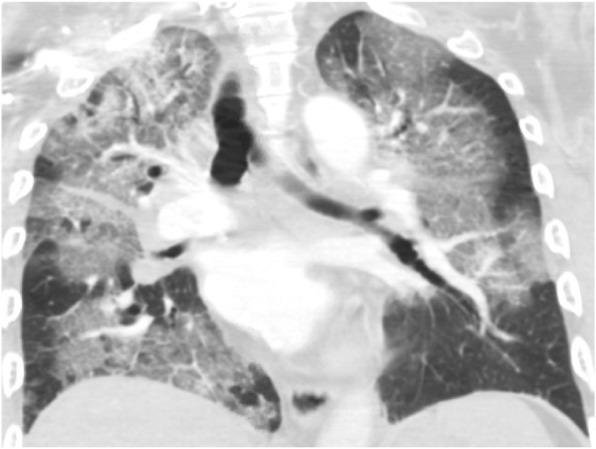

Although abnormalities are frequently found on chest imaging, the findings are non-specific and variable. In the Illinois/Wisconsin cohort, 83% were found to have abnormalities on chest radiograph and 100% were found to have abnormalities on Computed Tomography (CT) of the chest [ref. 15]. A chest x-ray should be obtained in patients with e-cigarettes use who present with respiratory, GI, or constitutional symptoms. Typical of findings on chest radiograph of EVALI is diffuse hazy bilateral opacities with occasional subpleural sparing (Fig. 1). Involvement of all lung lobes can be seen, but is not universal. Additionally, increased interstitial markings can be seen characterized by Kerley B lines. A CT chest should be pursued if there is high suspicion for EVALI but the chest radiograph is normal given the improved sensitivity of CT and/or to assist in ruling out other etiologies. While imaging findings are variable in EVALI, typical findings on chest CT are bilateral ground glass opacities (Fig. 2). Additionally, upper lobe predominant centrilobular nodules are often seen on chest CT [ref. 44]. Since findings on chest imaging are non-specific, other etiologies of lung injury should be considered.